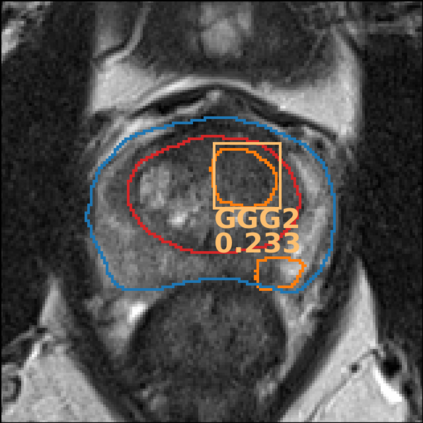

The emergence of multi-parametric magnetic resonance imaging (mpMRI) has had a profound impact on the diagnosis of prostate cancers (PCa), which is the most prevalent malignancy in males in the western world, enabling a better selection of patients for confirmation biopsy. However, analyzing these images is complex even for experts, hence opening an opportunity for computer-aided diagnosis systems to seize. This paper proposes a fully automatic system based on Deep Learning that takes a prostate mpMRI from a PCa-suspect patient and, by leveraging the Retina U-Net detection framework, locates PCa lesions, segments them, and predicts their most likely Gleason grade group (GGG). It uses 490 mpMRIs for training/validation, and 75 patients for testing from two different datasets: ProstateX and IVO (Valencia Oncology Institute Foundation). In the test set, it achieves an excellent lesion-level AUC/sensitivity/specificity for the GGG$\geq$2 significance criterion of 0.96/1.00/0.79 for the ProstateX dataset, and 0.95/1.00/0.80 for the IVO dataset. Evaluated at a patient level, the results are 0.87/1.00/0.375 in ProstateX, and 0.91/1.00/0.762 in IVO. Furthermore, on the online ProstateX grand challenge, the model obtained an AUC of 0.85 (0.87 when trained only on the ProstateX data, tying up with the original winner of the challenge). For expert comparison, IVO radiologist's PI-RADS 4 sensitivity/specificity were 0.88/0.56 at a lesion level, and 0.85/0.58 at a patient level. Additional subsystems for automatic prostate zonal segmentation and mpMRI non-rigid sequence registration were also employed to produce the final fully automated system. The code for the ProstateX-trained system has been made openly available at https://github.com/OscarPellicer/prostate_lesion_detection. We hope that this will represent a landmark for future research to use, compare and improve upon.